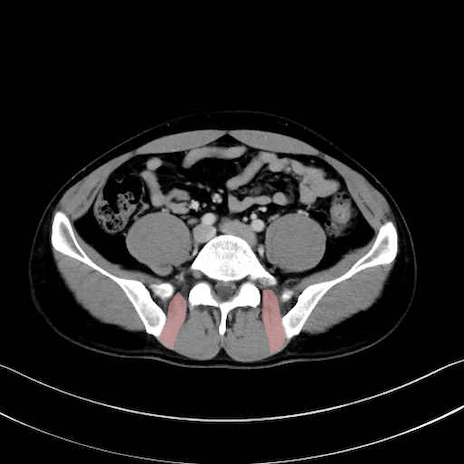

内閉鎖筋 (Obturator internus)